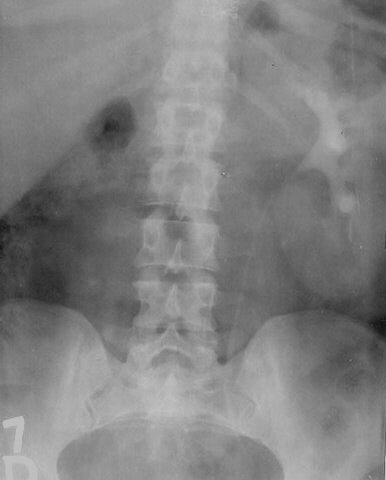

Rinichi supranumerar pelvin